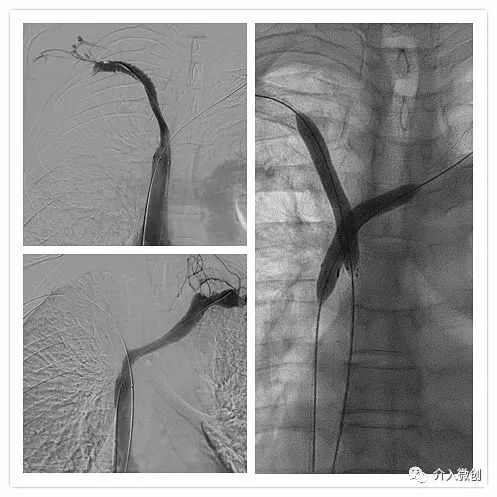

老年男性肺癌患者,拟行肺部肿瘤放射治疗,因上腔静脉综合征进展快速,无法较长时间平卧行胸部外照射治疗,予以行双侧头臂静脉+上腔静脉支架开通,快速恢复双上肢血液回流,即刻改善临床症状。

- 双侧头臂静脉闭塞,可见广泛侧支循环代偿血管显影,上腔静脉完全闭塞。

- 支架植入术后复查造影提示双侧上肢静脉回流顺畅。